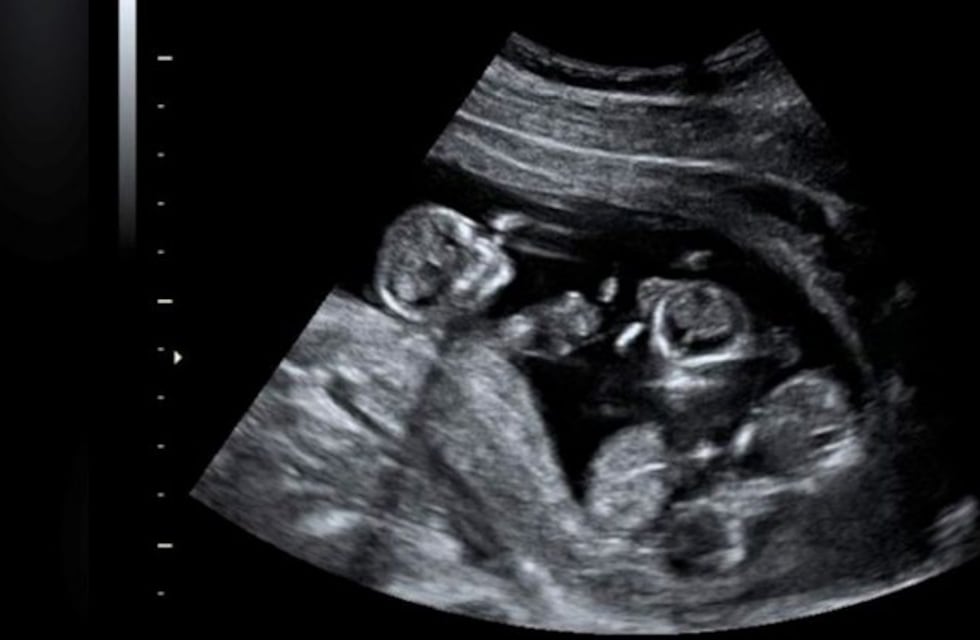

En este caso, las bebés se encontraban en tres bolsas amnióticas, dos de ellas compartiendo placenta. Isabella, quien nació en primera instancia, pesó 2,550 kilogramos, Francesca pesó 1,850 y Catalina 1,680, y quedaron internadas en la Unidad de Cuidados Intensivos Neonatales.